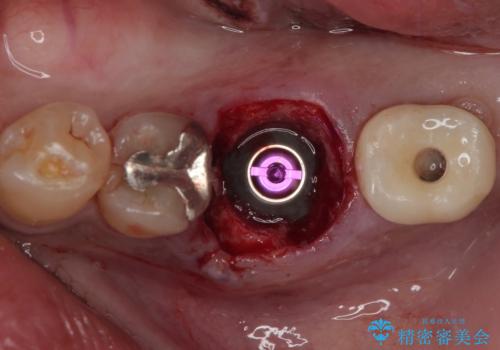

咬合力の影響で歯が壊れてしまう方の場合、長期間欠損が続くと、連鎖するように他の歯が壊されてしまうリスクがあるため、抜歯即時インプラントにより、治療期間の短縮を図ることとしました。

治療は順調に進み、わずか3ヶ月でセラミッククラウンを装着することができました。

他の歯への影響もなく、無事に治療を終えることができました。